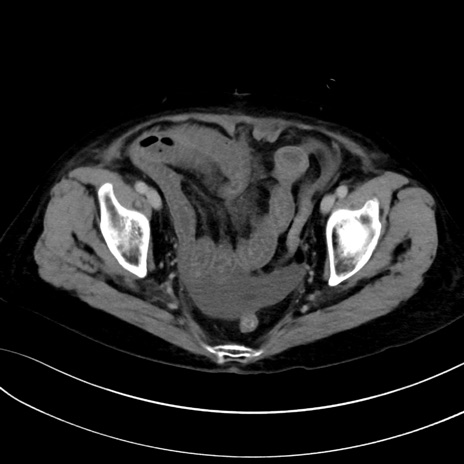

症例13 CT(横断像)1日半後